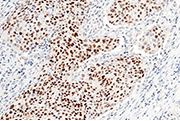

KRT19 antibody (Cat#: 100306-MM08)

Immunochemical staining of human KRT19 in human thyroid cancer. Image Credit: Sino Biological Inc.